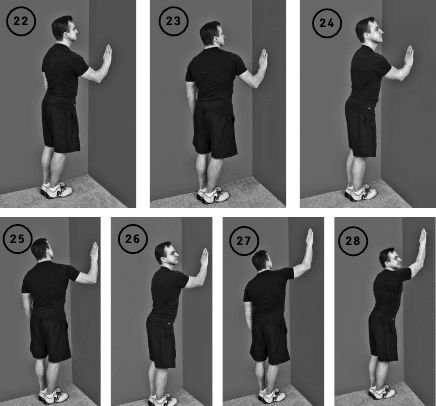

Упражнение «Шагаем по стене кистью»

Исходное положение – стоя полубоком к стене больным плечом. Кисть больной руки помещается на стену на уровне груди. Локтевой сустав свободно свисает вниз.

Вращаете туловищем из стороны в сторону (стопы остаются на полу неподвижными). Одновременно происходит движение в плечевом суставе.

Повторяете движения 10–30 раз. После чего перемещаете кисть на несколько сантиметров выше и повторяете движения туловищем.

Постепенно поднимаете кисть до полностью выпрямленного положения руки. Выполняете упражнения для другой руки (ил. 22–28).

Упражнение «Шагаем по стене кистью» последовательно приводит к увеличению отведения участвующего в упражнении плеча. Это движение ограничено при плечелопаточном периартрозе, «синдроме замороженного плеча» или «импинджмент-синдроме», когда отведение руки очень болезненно и поэтому ограничено.

В начале тренировок вы поднимаете кисть на максимально возможный уровень, не вызывая интенсивных болей. День за днем, по мере разработки объем отведения и высота поднятой кисти будут увеличиваться.